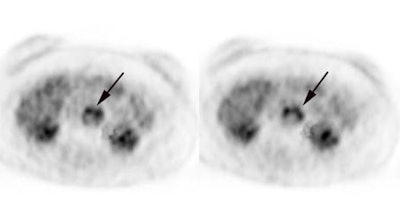

Recurrent colorectal cancer: The patient shown below had a history of colon cancer and a rising CEA level. FDG PET exam revealed a site of tracer uptake in the mesentery (black arrows) which corresponded to an enlarged lymph node seen retrospectively on CT scan (white arrow). |

|